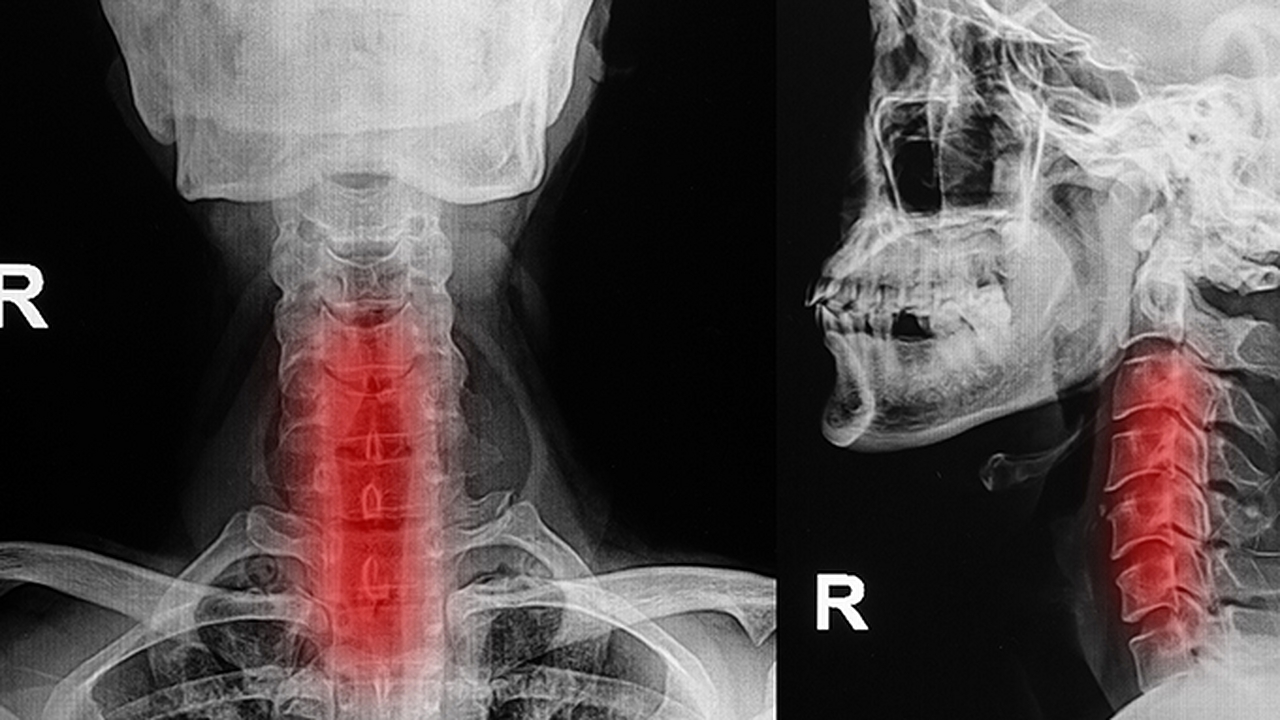

4、咽喉炎

細(xì)菌或病毒感染可引起咽后壁淋巴濾泡增生,伴隨吞咽疼痛、發(fā)熱等癥狀。鏈球菌感染需使用阿莫西林克拉維酸鉀片,病毒感染可選擇藍(lán)芩口服液。急性期可用復(fù)方硼砂溶液含漱,避免進(jìn)食辛辣刺激食物。